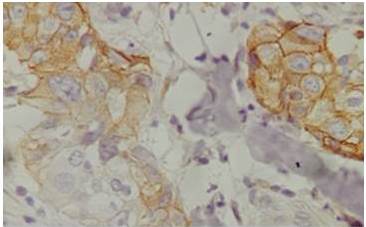

La variedad adenoescamosa del MpBC histopatológicamente es un carcinoma invasivo con áreas de formación túbulo glandular bien diferenciada íntimamente mezcladas con nidos sólidos dispersos de diferenciación escamosa. El componente escamoso es a menudo queratinizante, pero va desde zonas queratinizadas muy bien diferenciadas a zonas de poca diferenciación no queratinizada (1). Tal como se puede apreciar en la (Figura 1 y 2), correspondientes a las láminas de tinción por Hematoxilina y Eosina de nuestro caso clínico a 4x y 10x de aumento al microscopio.

Una observación relativamente consistente en muchos estudios sugiere que el MpBC tiende a presentar biomarcadores negativos (RE, RP y HER2) (15). Esto a menudo ha llevado a su comparación con el cáncer de mama triple negativo (TNBC), que es una categoría separada y distinta de cáncer de mama, con diferente comportamiento clínico y tratamiento. En el caso clínico presentado se confirma la negatividad de los RP (Figura 3), solo una cruz positiva para RE y HER2 neu negativo, acorde a lo reportado en la literatura revisada.

Aunque la mayoría de los MpBC tienen un fenotipo triple negativo, anecdóticamente, los resultados clínicos parecen diferentes de los de TNBC. Por otra parte, Las tinciones mioepiteliales y de citoqueratinas son positivas (Figura 4) correspondiente a la IHQ de e-cadherina de nuestro caso clínico, pero el grado de tinción es muy variable (16).